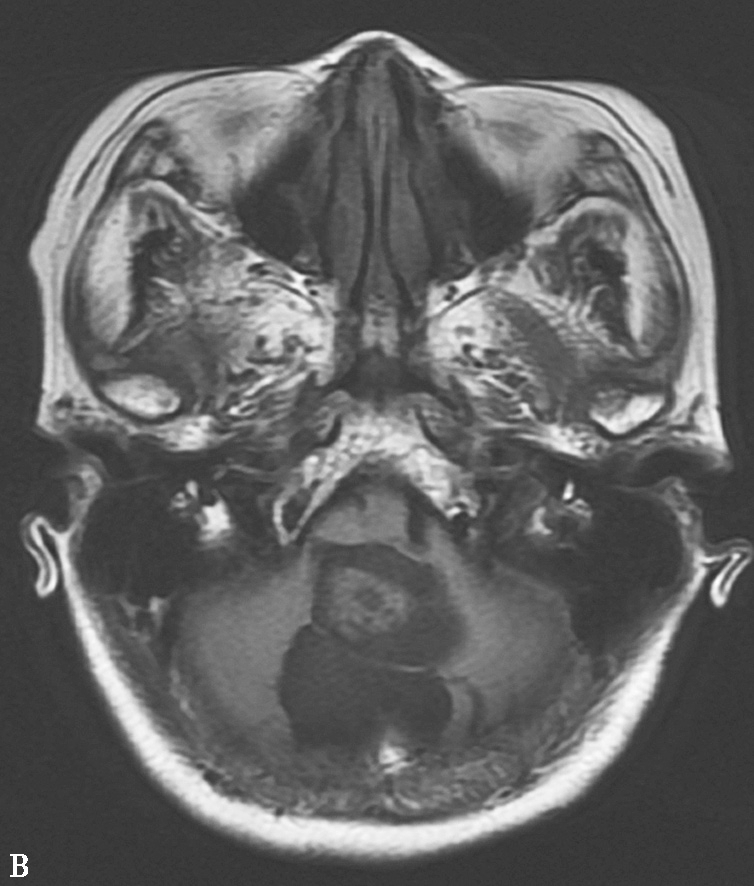

图1-12 血管母细胞瘤

A.MRI T 1 WI横轴位;B.T 1 WI横轴位

图1-12 血管母细胞瘤(续)

C.T 2 WI矢状位;D.T 1 WI增强,示小脑蚓部见一囊性肿块,其内囊液呈长T 1 、长T 2 液性信号,囊壁有卵圆形等信号结节,呈“大囊伴小附壁结节”表现,增强扫描壁结节显著强化,囊壁不强化